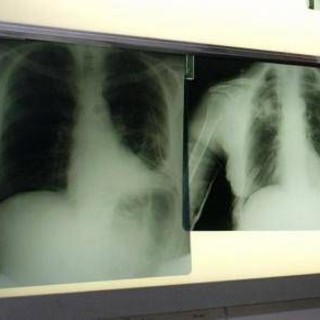

Ricerca, bandi Gilead, infettivologo Andreoni: "Da Fellowship Program forte impatto su pazienti"